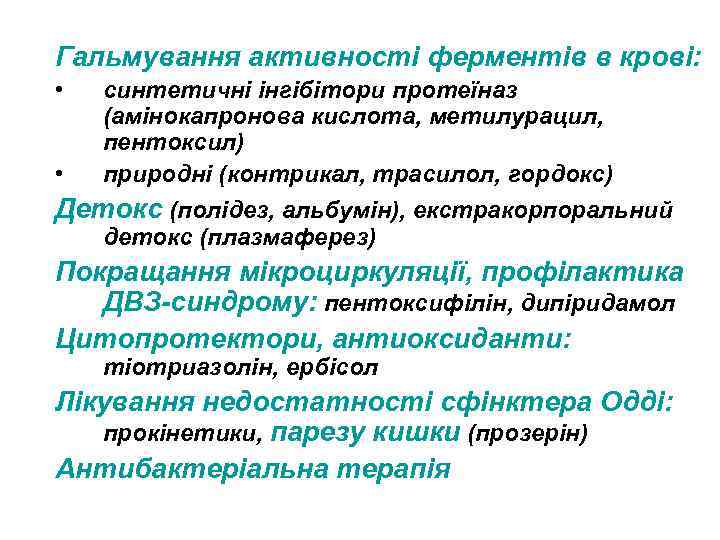

Гальмування активності ферментів в крові: • • синтетичні інгібітори протеїназ (амінокапронова кислота, метилурацил, пентоксил) природні (контрикал, трасилол, гордокс) Детокс (полідез, альбумін), екстракорпоральний детокс (плазмаферез) Покращання мікроциркуляції, профілактика ДВЗ-синдрому: пентоксифілін, дипіридамол Цитопротектори, антиоксиданти: тіотриазолін, ербісол Лікування недостатності сфінктера Одді: прокінетики, парезу кишки (прозерін) Антибактеріальна терапія

Гальмування активності ферментів в крові: • • синтетичні інгібітори протеїназ (амінокапронова кислота, метилурацил, пентоксил) природні (контрикал, трасилол, гордокс) Детокс (полідез, альбумін), екстракорпоральний детокс (плазмаферез) Покращання мікроциркуляції, профілактика ДВЗ-синдрому: пентоксифілін, дипіридамол Цитопротектори, антиоксиданти: тіотриазолін, ербісол Лікування недостатності сфінктера Одді: прокінетики, парезу кишки (прозерін) Антибактеріальна терапія